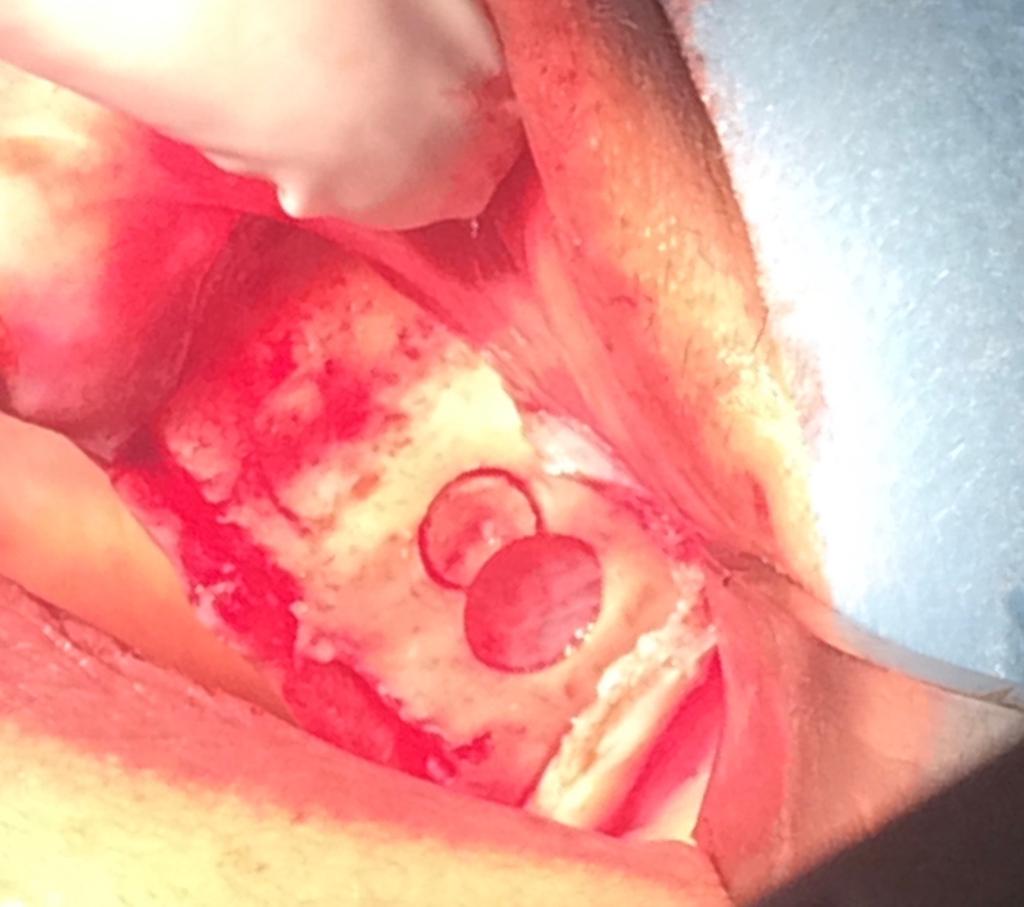

2éme TEMPS

CHIRURGICAL

PRELEVEMENT RAMIQUE